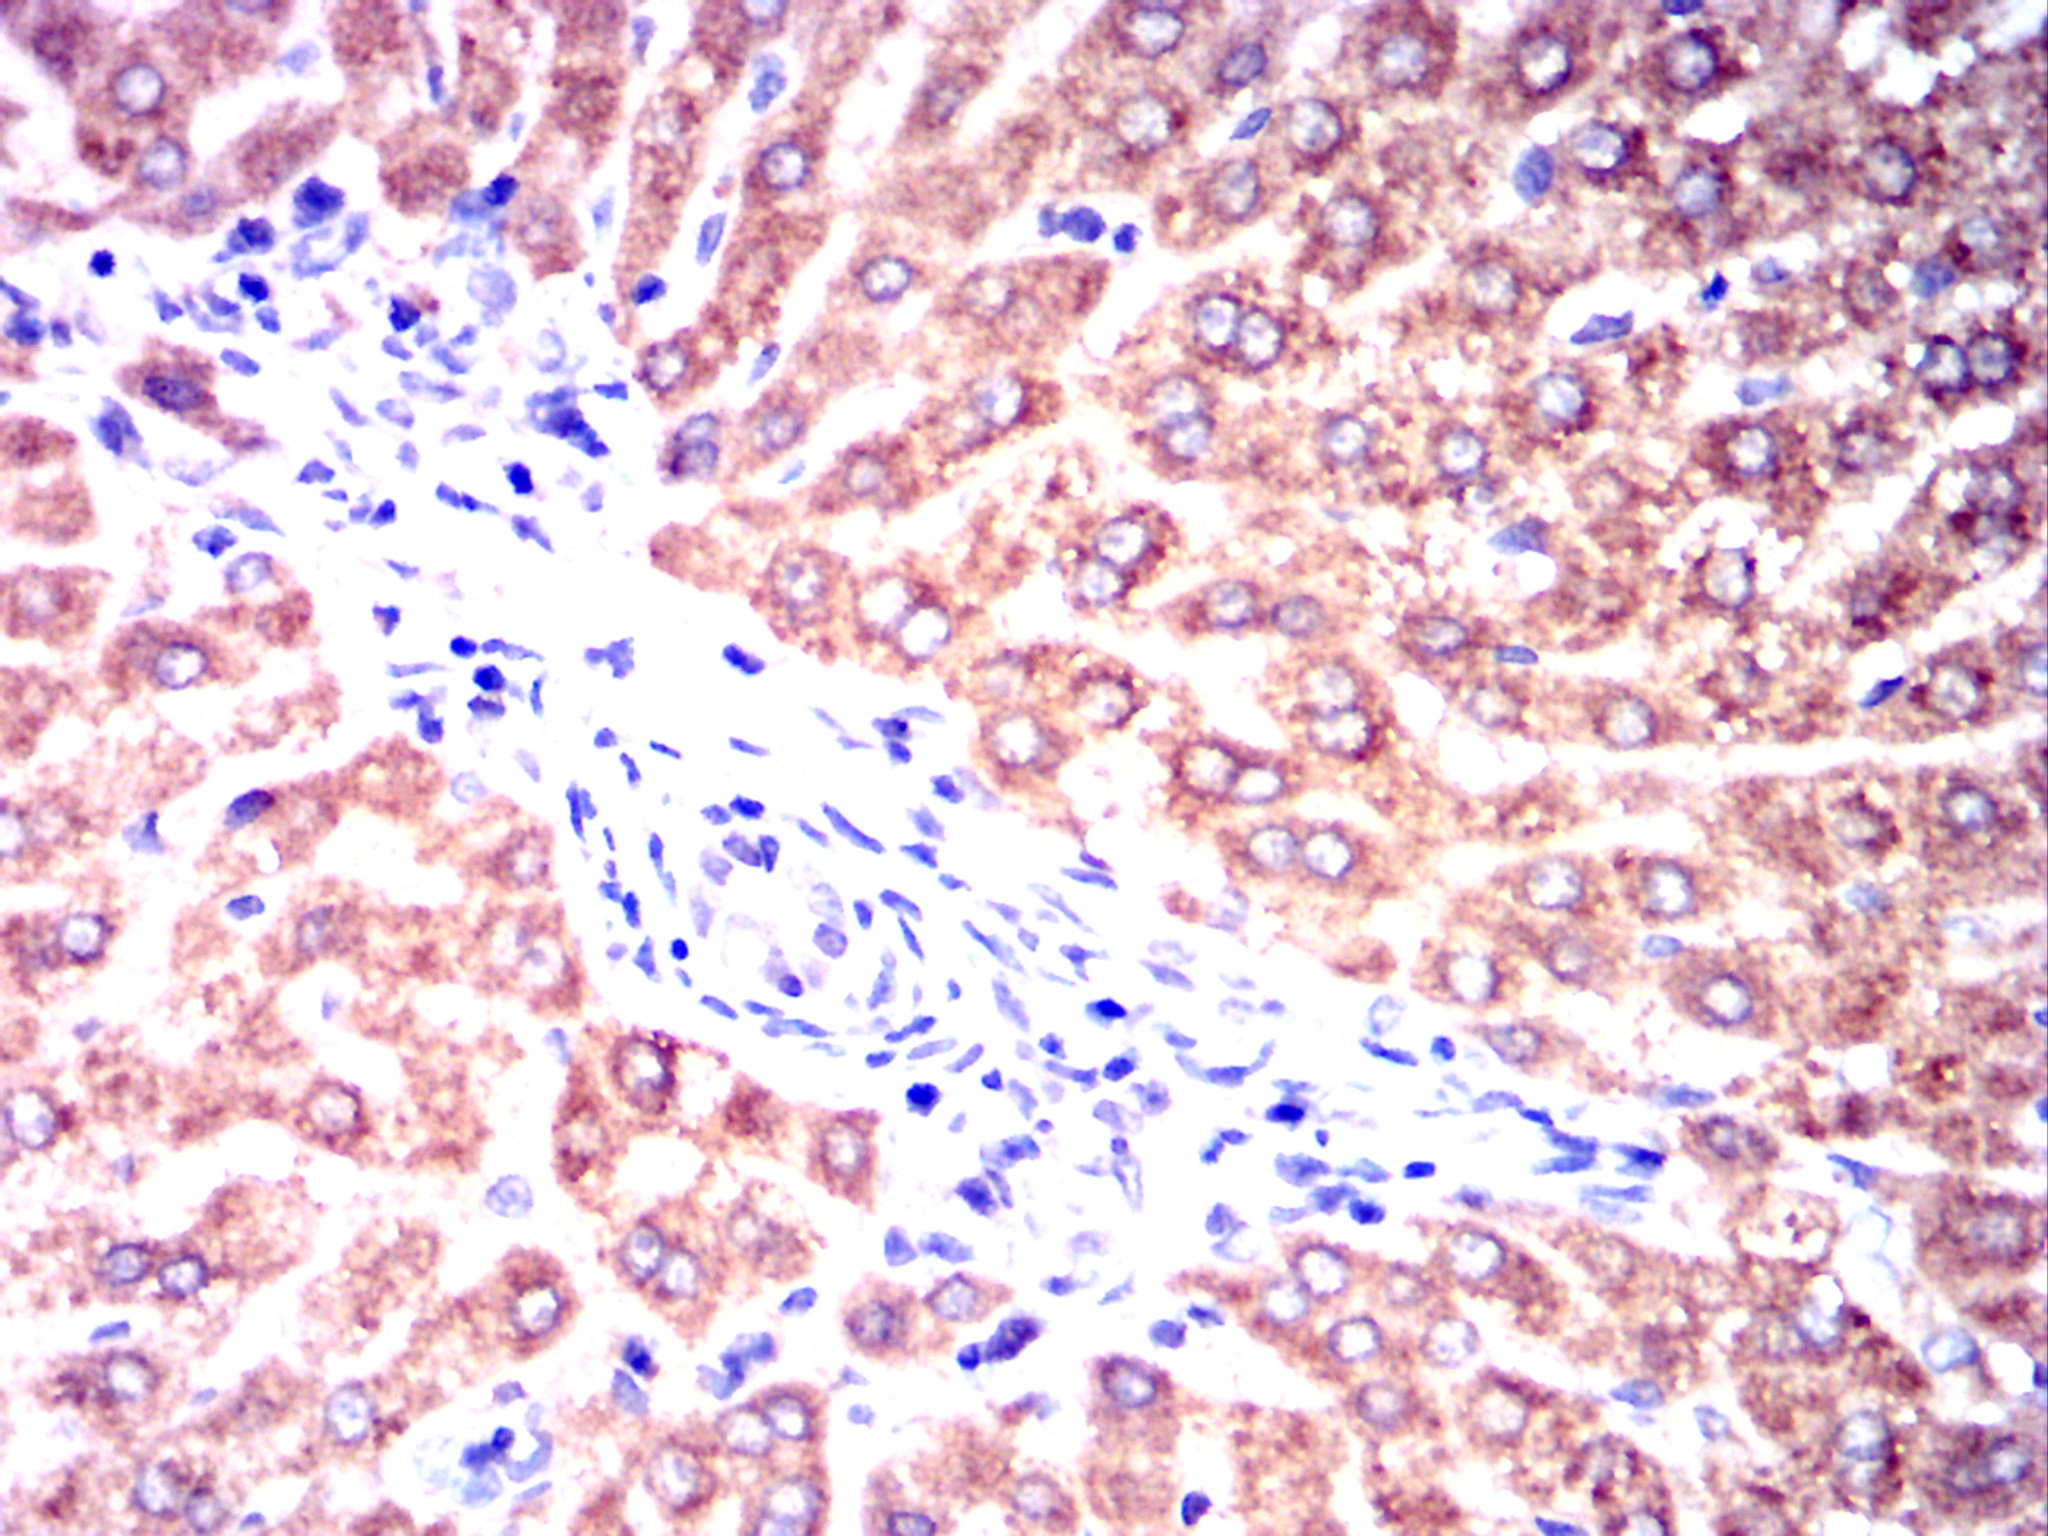

-

Immunohistochemical analysis of paraffin-embedded rabbit liver tissues using CHRM3 mouse mAb with DAB staining.

Immunohistochemical analysis of paraffin-embedded rabbit kidney tissues using CHRM3 mouse mAb with DAB staining.